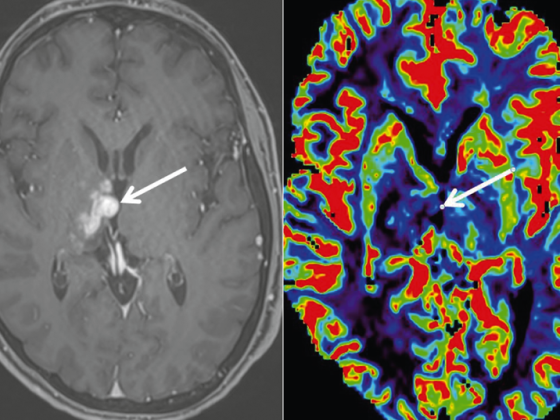

• Primäres ZNS-Lymphom

Erweiterte MRI-Diagnostik (Spektroskopie, DWI, PWI) und MRI-gestützte Biopsie